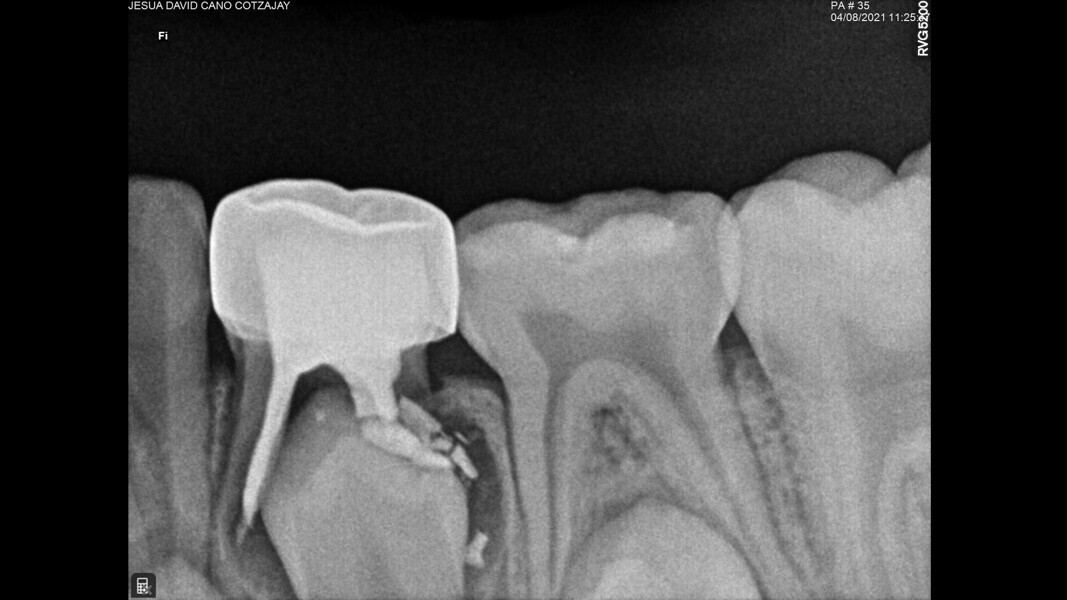

This male patient was 6 years and 7 months old and presented with severe tooth decay on the mandibular left first primary molar without any symptoms of pain. He experienced slight discomfort to percussion and palpation of the buccal gingiva. A buccal abscess and no mobility were observed. The radiograph showed a large area of interradicular bone loss. The tooth was diagnosed with pulp necrosis and an asymptomatic apical abscess. Pulpectomy was performed, and at a second appointment, a stainless-steel crown was placed upon confirming absence of signs or symptoms of disease. At the 14-month recall, no clinical pathology was detected and a normal eruptive process of the permanent premolars was observed in spite of the extrusion of the obturation material.